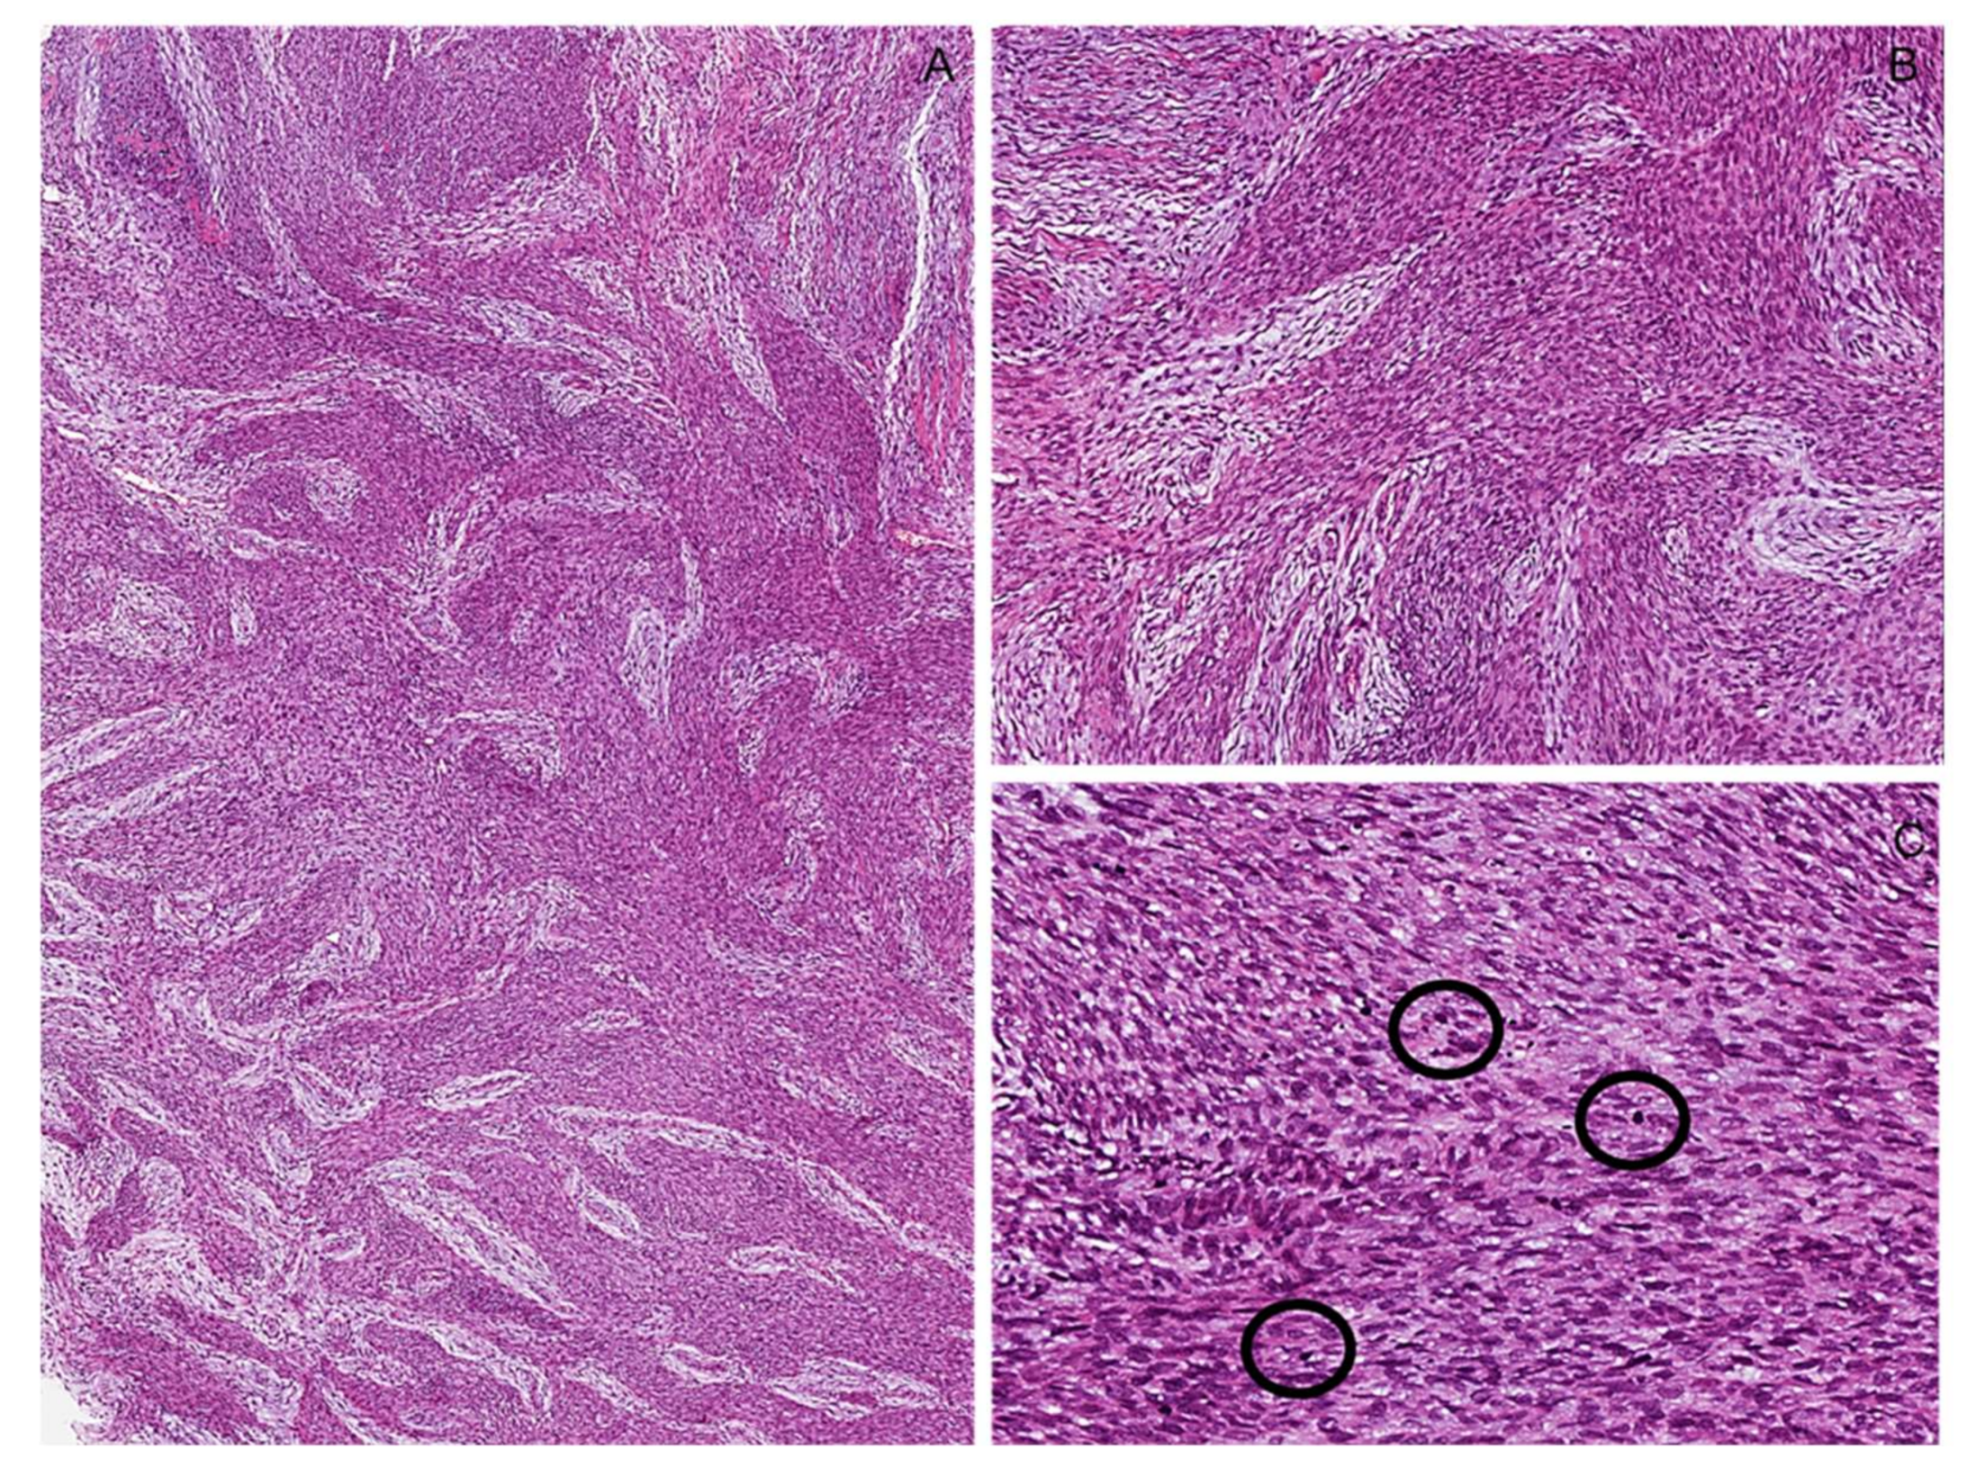

7.1. Intraneural Perineurioma

7.1.1. Immunohistochemical Features

7.1.2. Molecular Features